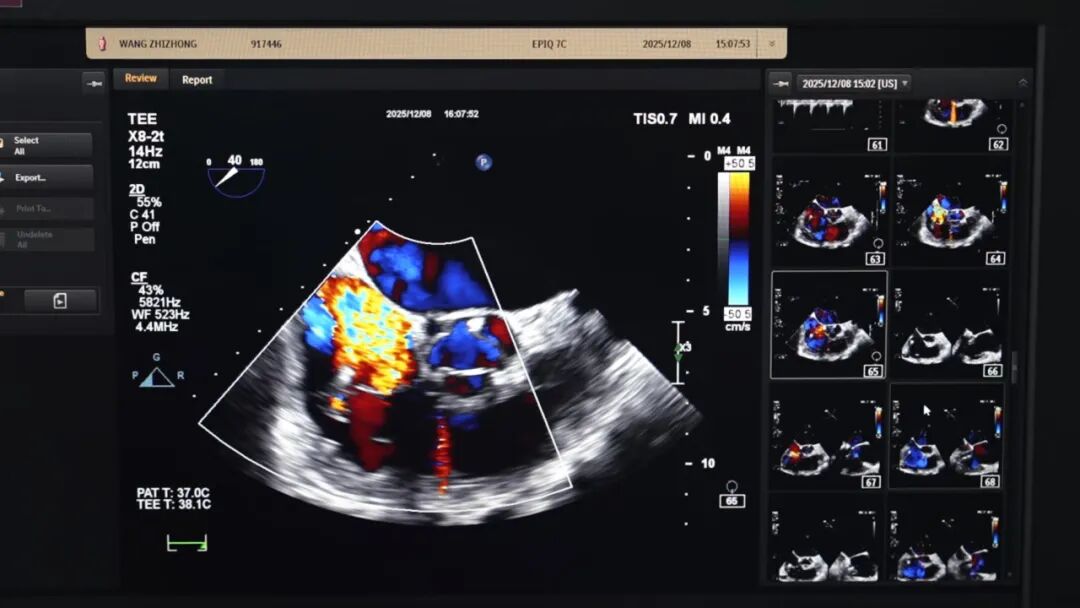

面对这一临床难题,医院迅速组织多学科专家联合会诊。团队反复研讨病情,精准评估患者心脏功能、瓣膜形态及起搏器导线位置,最终敲定“经导管二尖瓣+三尖瓣钳夹一站式手术”方案,并决定采用国产先进钳夹器械,在微创条件下完成双重修复,最大限度降低手术创伤。

手术当天,袁义强院长、刘煜昊主任、陈同峰博士等专家凭借精湛技术,通过股动脉、股静脉穿刺建立微创通道,将纤细的器械精准送达心脏瓣膜位置。术中,专家团队既要避开起搏器导线的干扰,又要精准定位瓣膜反流靶点,操作难度堪比 “在心脏里穿针引线”。经过数小时的精细操作,成功为患者完成二尖瓣、三尖瓣钳夹修复。